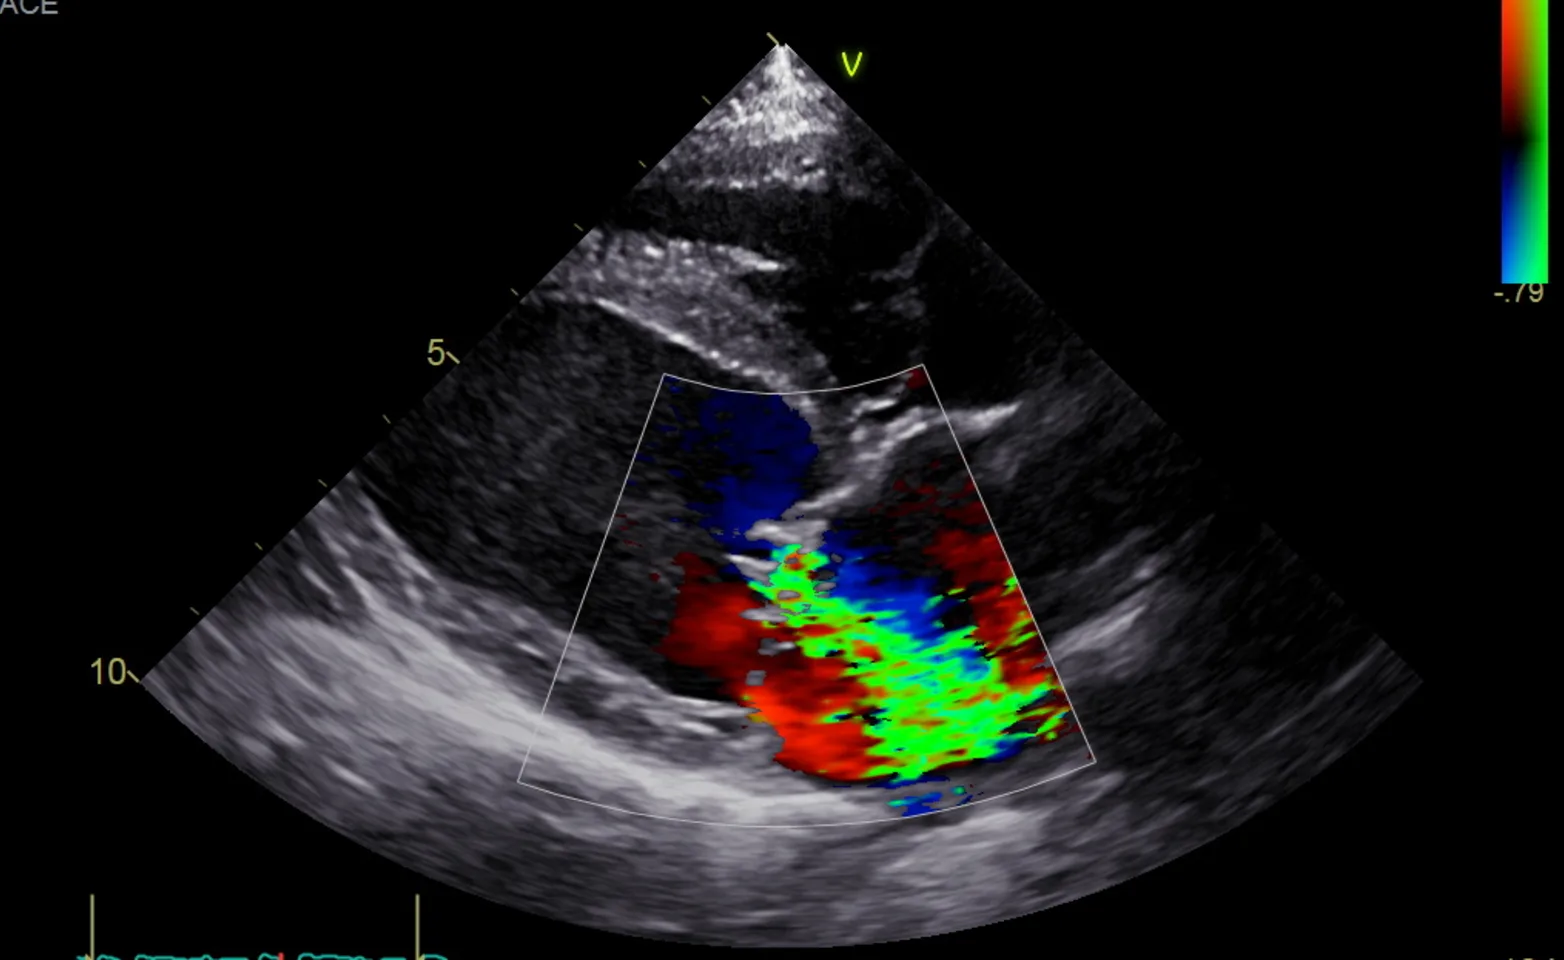

Echocardiography